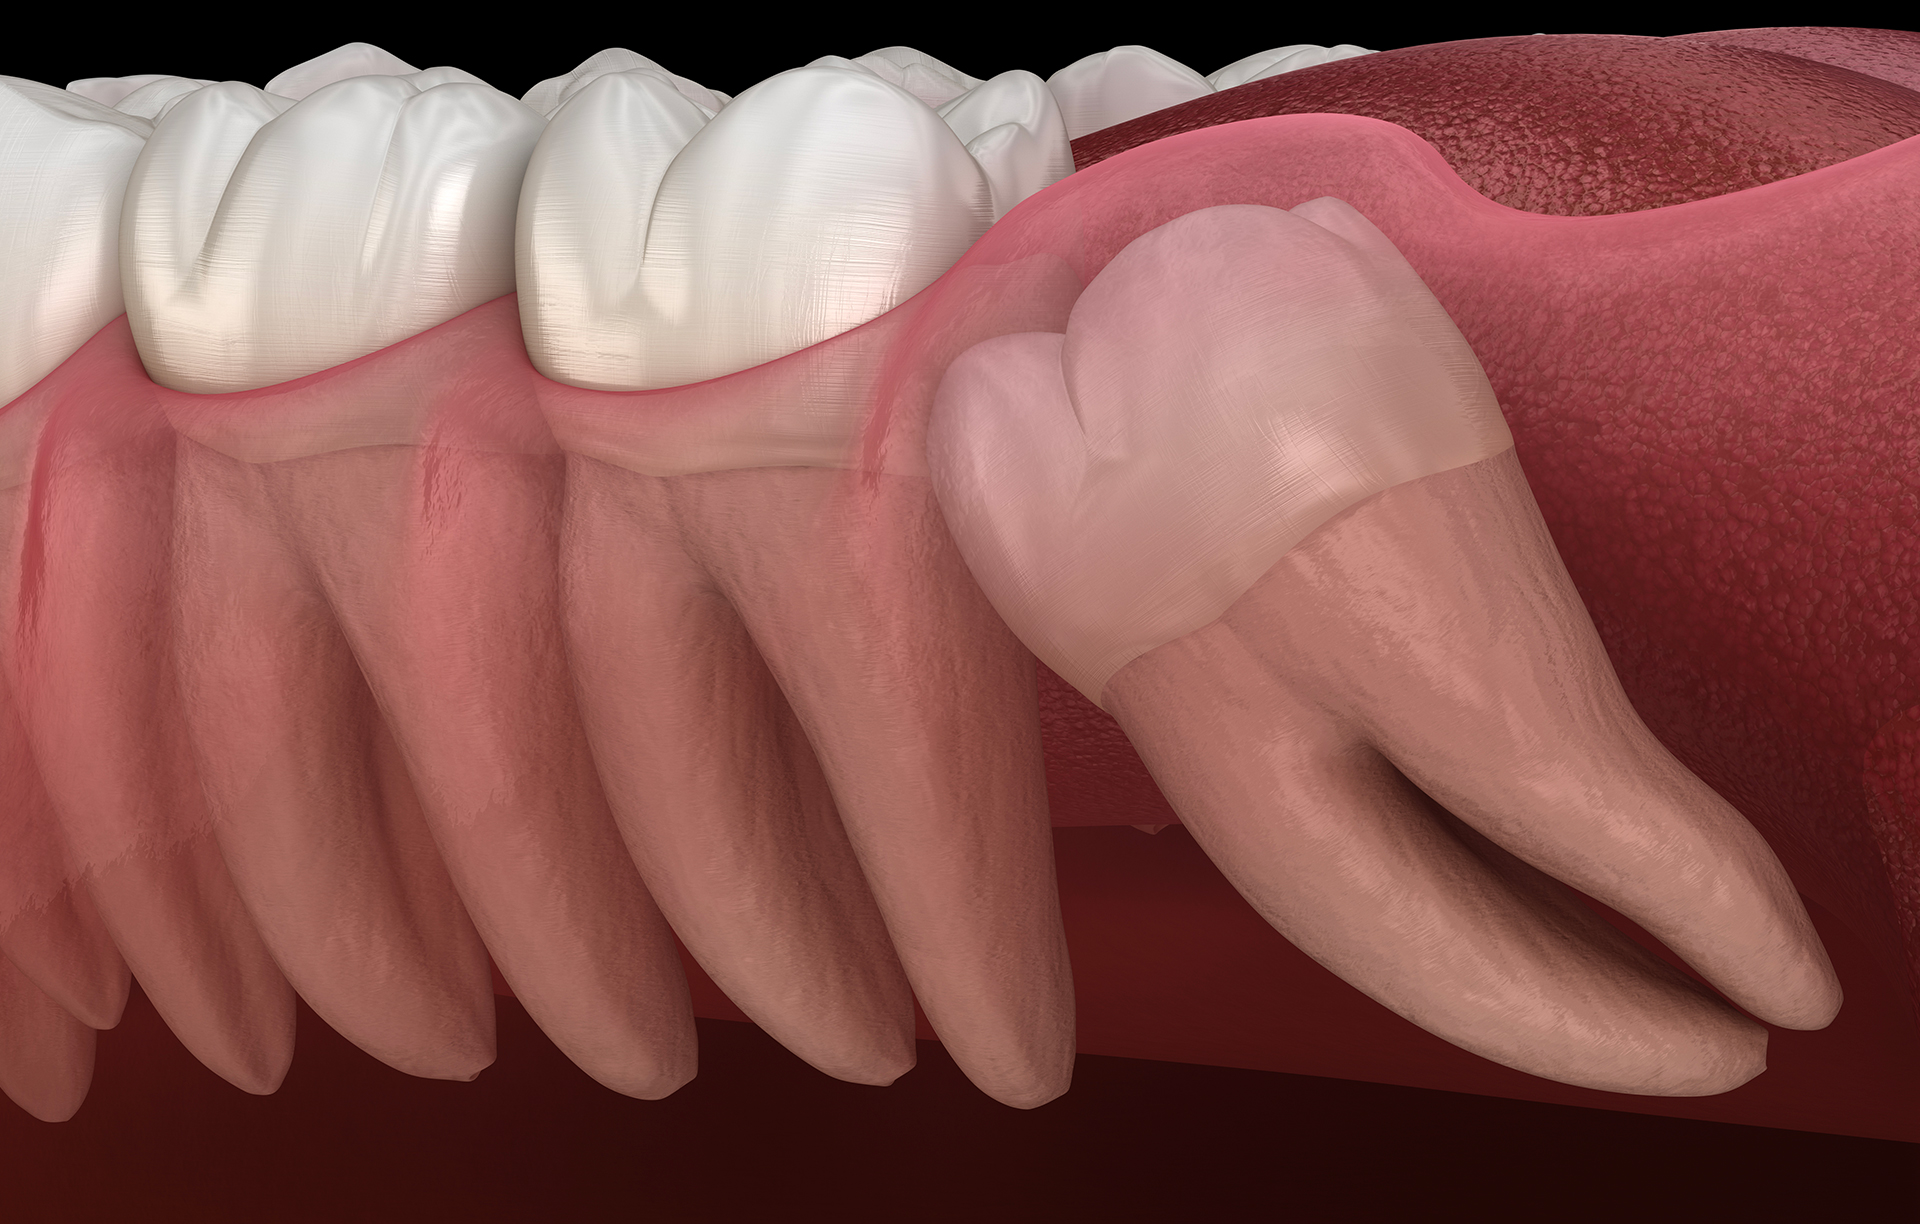

Wisdom teeth extraction

The prophylactic extraction of wisdom teeth during an orthodontic treatment, the extraction of an ectopic dental inclusion and an extraction in a pathological context (cyst, tumour, abscess) all require the expertise of a maxillofacial surgeon in order to avoid major sequelae.